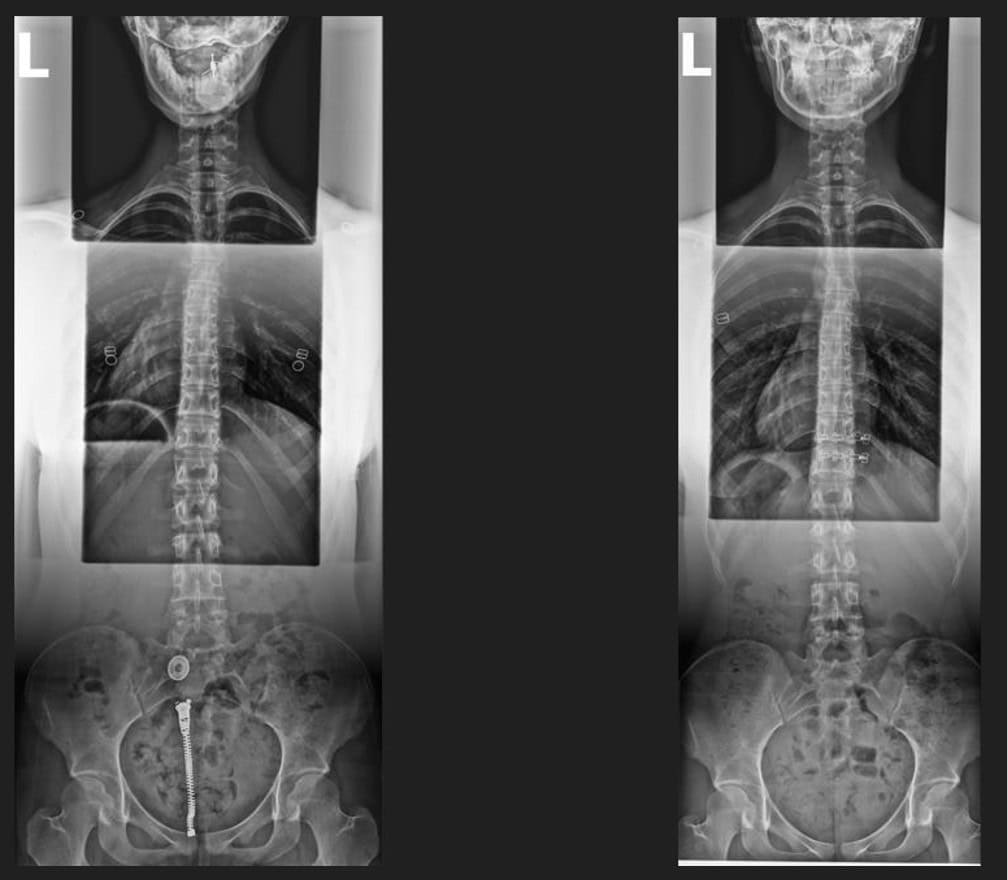

Pre & Post Scan